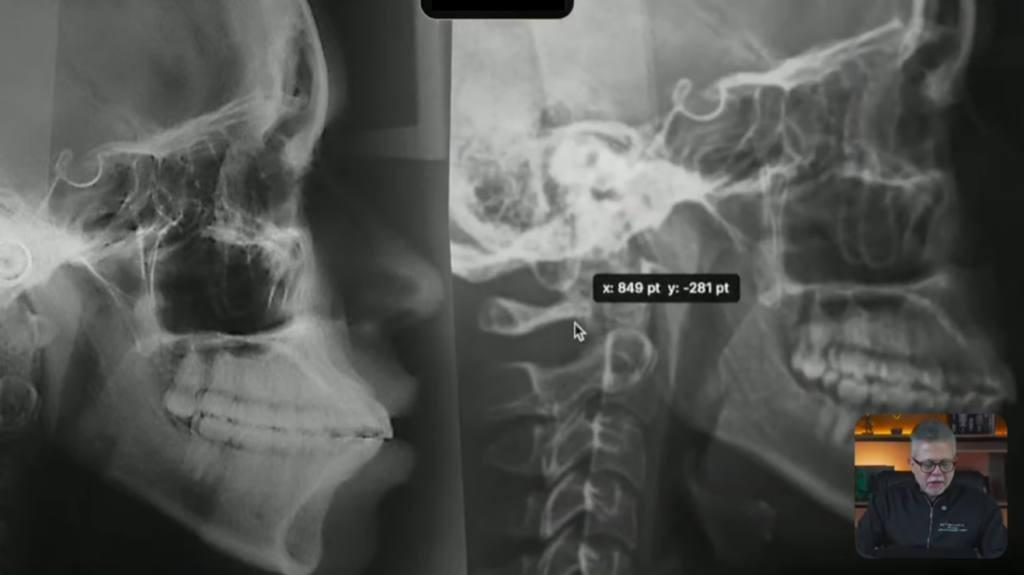

Essas fotos aqui são o antes e o depois, então aqui nós tínhamos a paciente biprotrusa e depois das 4 extrações ela ficou com os incisivos bem posicionados:

Vejam a mudança que aconteceu

Se vocês observarem, aqui o longo eixo do incisivo, aqui o longo eixo do incisivo agora está tangenciando a órbita, e aqui o longo eixo do incisivo inferior está mais ou menos com 90 graus com a base da mandíbula: